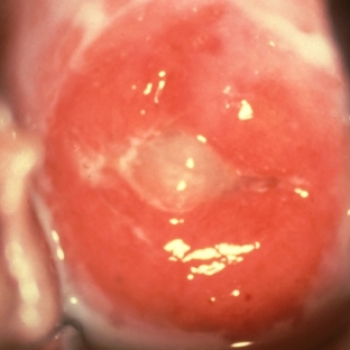

El virus del papiloma humano y cáncer de cervix

VIRUS DEL PAPILOMA HUMANO

Descripción, características y riesgos de este virus

Durante mucho tiempo, el virus del papiloma o condilomatosis se consideró inofensivo y rara vez se trataba. Por ello carecía de importancia determinar su frecuencia. Hoy se sabe que es una enfermedad venérea que afecta sobre todo los genitales de la mujer, hasta el punto de que puede producir cáncer en el cuello del útero.

LAS 12 CLAVES DEL VIRUS DEL PAPILOMA

Las investigaciones de las últimas dos décadas han aclarado el panorama sobre la génesis del cáncer de cérvix y su relación con el virus del papiloma